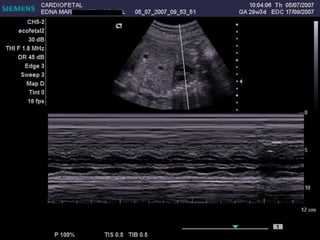

ECOCARDIOGRAFIA FETAL Modo B Modo M Doppler ¿CUANDO? A partir de la sem 12 por vía TV A partir de la sem 18 por vía abdominal Optimo: semana 22

Ritmo

Banda moderadora